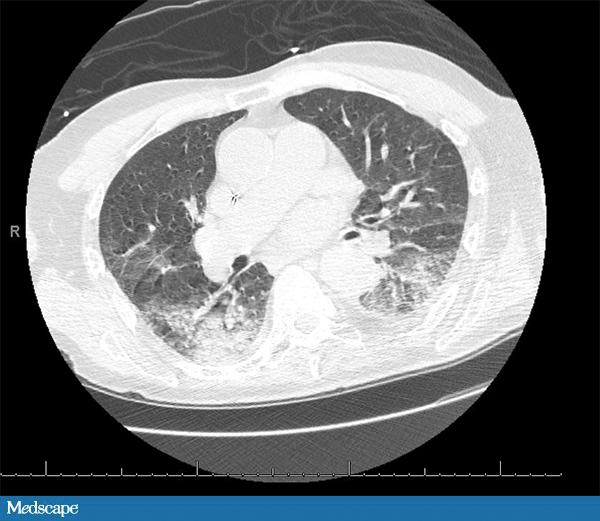

89 岁男性,有房颤、癫痫、痴呆病史。家属发现其昏迷并伴有右侧上下肢震颤,送至急诊科。患者的抗癫痫药于发病前一天吃完。体查示患者低烧(37.9°C),血压、心率、呼吸均正常。就诊时仍处于癫痫发作态势,遂予劳拉西泮解痉。患者白细胞 20,700/µL,中性粒细胞 77%。血红蛋白和血小板均正常。肌酐轻度升高(1.5 mg/dL)。心电图示房性节律,ST-T 波广泛性改变。肌钙蛋白 >40 mg/dL。CT 示“可能由吸入引起的双肺实变”。患者收入重症监护室。予头孢曲松控制肺炎,当晚换成舒巴坦。次日早晨,患者情况稳定,白细胞恢复正常。此时应如何进行下一步处理?

患者的临床症状和 CT 均提示轻度吸入性非细菌性肺炎(编者注:pneumonitis,这里应关注与 pneumonia 相区分,前者通常指吸入性的非感染性的炎症,比如胃液腐蚀性的;后者 pneumonia 常指感染性的肺炎,下文中同),这种情况可以发生于意识丧失期间。患者最主要的问题是心脏,白细胞升高很可能是心梗(肌钙蛋白阳性)造成。无发热且无明显的 CT 发现提示肺炎的可能性不大。另外,如果是常规感染性肺炎,白细胞不太可能这么快恢复正常。

吸入性非细菌性肺炎(pneumonitis)是吸入返流的胃内容物造成的,需进行气道管理。预防性使用抗生素不会对病情有利,反而会筛选出更加耐药的微生物。吸入性非细菌性肺炎是一种化学炎症反应,而通常所说的吸入性肺炎(pneumonia)是一个感染过程,二者常常混淆。通常所说的吸入性肺炎由吸入口咽部的分泌物导致,常见于神经性吞咽困难、胃和食管连接异常或上呼吸消化道解剖形态异常的患者。和吸入性非细菌性肺炎不同,通常说的吸入性肺炎需要抗生素治疗。我们可以通过发热、脓性分泌物和呼吸窘迫(呼吸急促、缺氧)与否对二者进行鉴别。